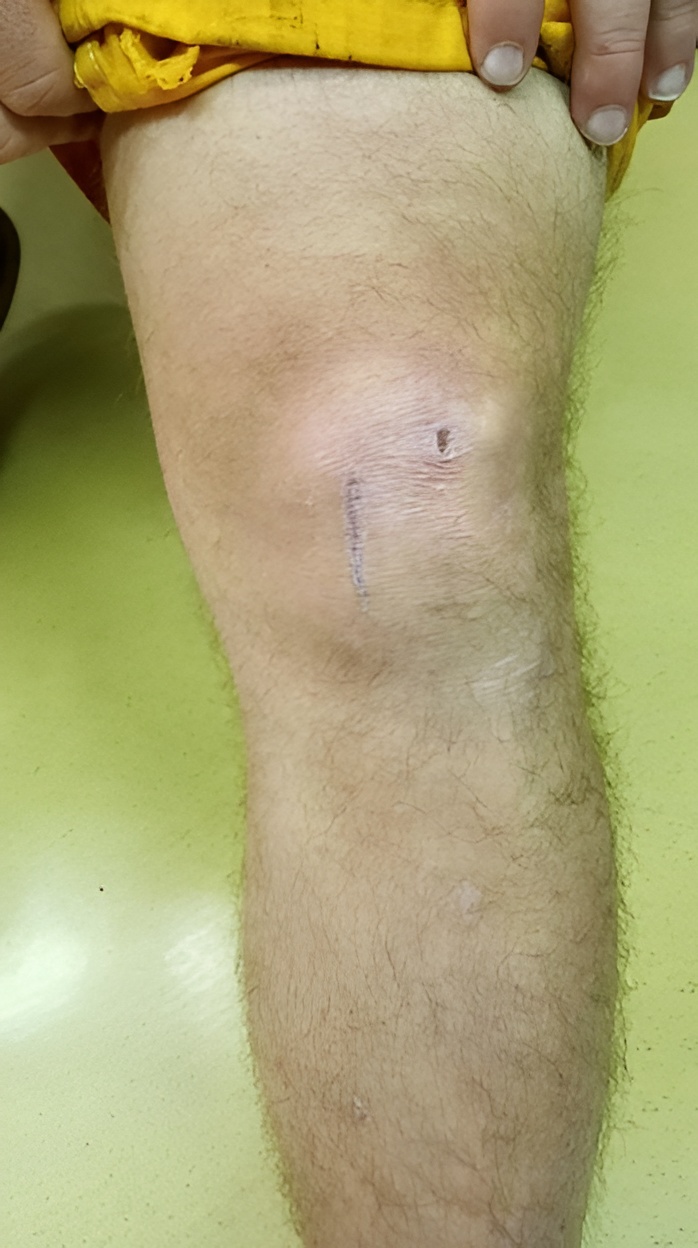

In remote environments, where traditional healthcare infrastructure is out of reach, the ability to manage complex injuries on-site is critical. One recent case involved a deep laceration over the knee, requiring immediate and careful attention due to its proximity to a major joint.

Following a structured approach under the direction of our Medical Control Specialists, the Industrial Remote Environment Medical Specialists (IREMS) began with an initial cleaning and thorough assessment to ensure the wound had not penetrated the joint or involved any critical structures. Once cleared, the IREMS conducted a definitive cleaning, established a sterile field, and executed a precise wound closure.

By Day 14 post-repair, the results were clear: the wound was healing extremely well, with minimal signs of scarring. Over the course of the next year the scar will continue to contract becoming smaller and less visible. Just like any “post-op wound” patients are instructed on the use of topical agents like Vitamin E and proper sun protection, will further reduce the scar’s appearance.